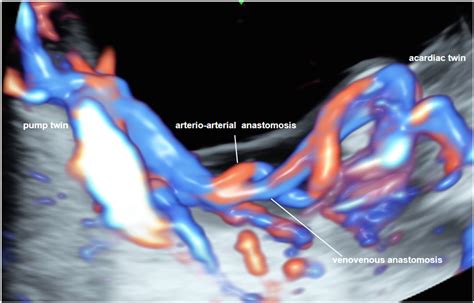

Twin Reversed Arterial Perfusion (TRAP) sequence is a rare but serious complication that can occur in monochorionic twin pregnancies. This condition arises when one twin, known as the "pump twin," develops normally and supplies blood to the other twin, known as the "acardiac twin," through abnormal blood vessels. The acardiac twin lacks a functional heart and relies entirely on the pump twin for circulation, leading to a range of severe health issues for both twins.

TRAP sequence is a complex condition that requires a deep understanding of its underlying mechanisms and implications. Monochorionic twin pregnancies, where the twins share a single placenta, are at higher risk for this condition. The abnormal blood flow from the pump twin to the acardiac twin can lead to high-output cardiac failure in the pump twin, potentially causing heart failure, hydrops, and even death.

Doppler ultrasound is particularly useful in visualizing the abnormal blood flow patterns characteristic of TRAP sequence. Magnetic Resonance Imaging (MRI) may also be used to provide a more detailed assessment of the twins' anatomy and the extent of the condition.